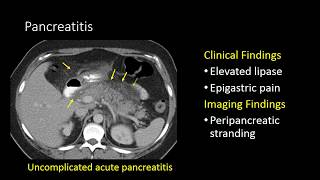

Pancreatic Emergencies | Interesting Radiology Cases

Pancreatic Emergencies | Interesting Radiology Cases Interactive CT Abdo Cases - Pancreatitis and Complications (Intro Level)

Interactive CT Abdo Cases - Pancreatitis and Complications (Intro Level) CT Normal Pancreas Vs Acute Pancreatitis | Balthazar Modified CT Severity Index (MCTSI) Scoring

Solid and cystic pancreatic lesion GI Imaging - Pancreatitis

Grab Bag Emergencies | Interesting Radiology Cases Imaging in Pancreatitis

Imaging in Pancreatitis Acute Pancreatitis and Complications on CT

Acute Pancreatitis and Complications on CT